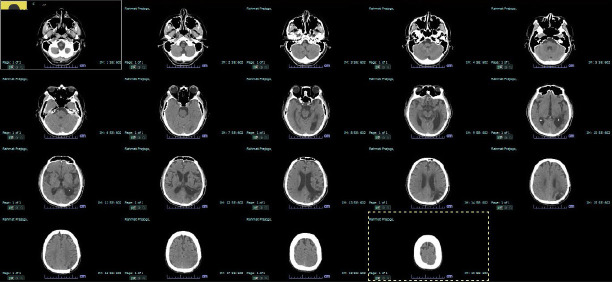

Optic aphasia is a rare neurological disorder that affects the visual-semantic ability of patients with normal vision and is caused by a lesion in the left occipital lobe. The signs and symptoms of optic aphasia are similar to those of associative visual agnosia, where patients have difficulty recognizing objects both in shape and function, resulting in challenges performing daily tasks. The transformation to optic aphasia or associative visual agnosia is closely related to the degree of damage to the corpus callosum, with some studies hypothetically suggesting that complete damage to the corpus callosum leads to optic aphasia, whereas incomplete damage causes associative visual agnosia. We present a case of a 60-year-old man with a history of intracerebral hemorrhage in the left occipitotemporoparietal lobe. The patient complained of intermittent episodes of painless, blurry vision. Upon examination, we observed that the patient was unable to read the Snellen chart, although he could draw the letter. Furthermore, we discovered that the patient had difficulty naming objects and instruments, even though he was able to express their shape and function through gestures and mimicry. The signs and symptoms of the patient, along with the result of the multi-slice non-contrast CT scan, suggest that he had optic aphasia rather than associative visual agnosia. A comprehensive neuropsychological and aphasia examination needs to be performed to further assess the condition of our patient and establish the diagnosis.

Abstract Image